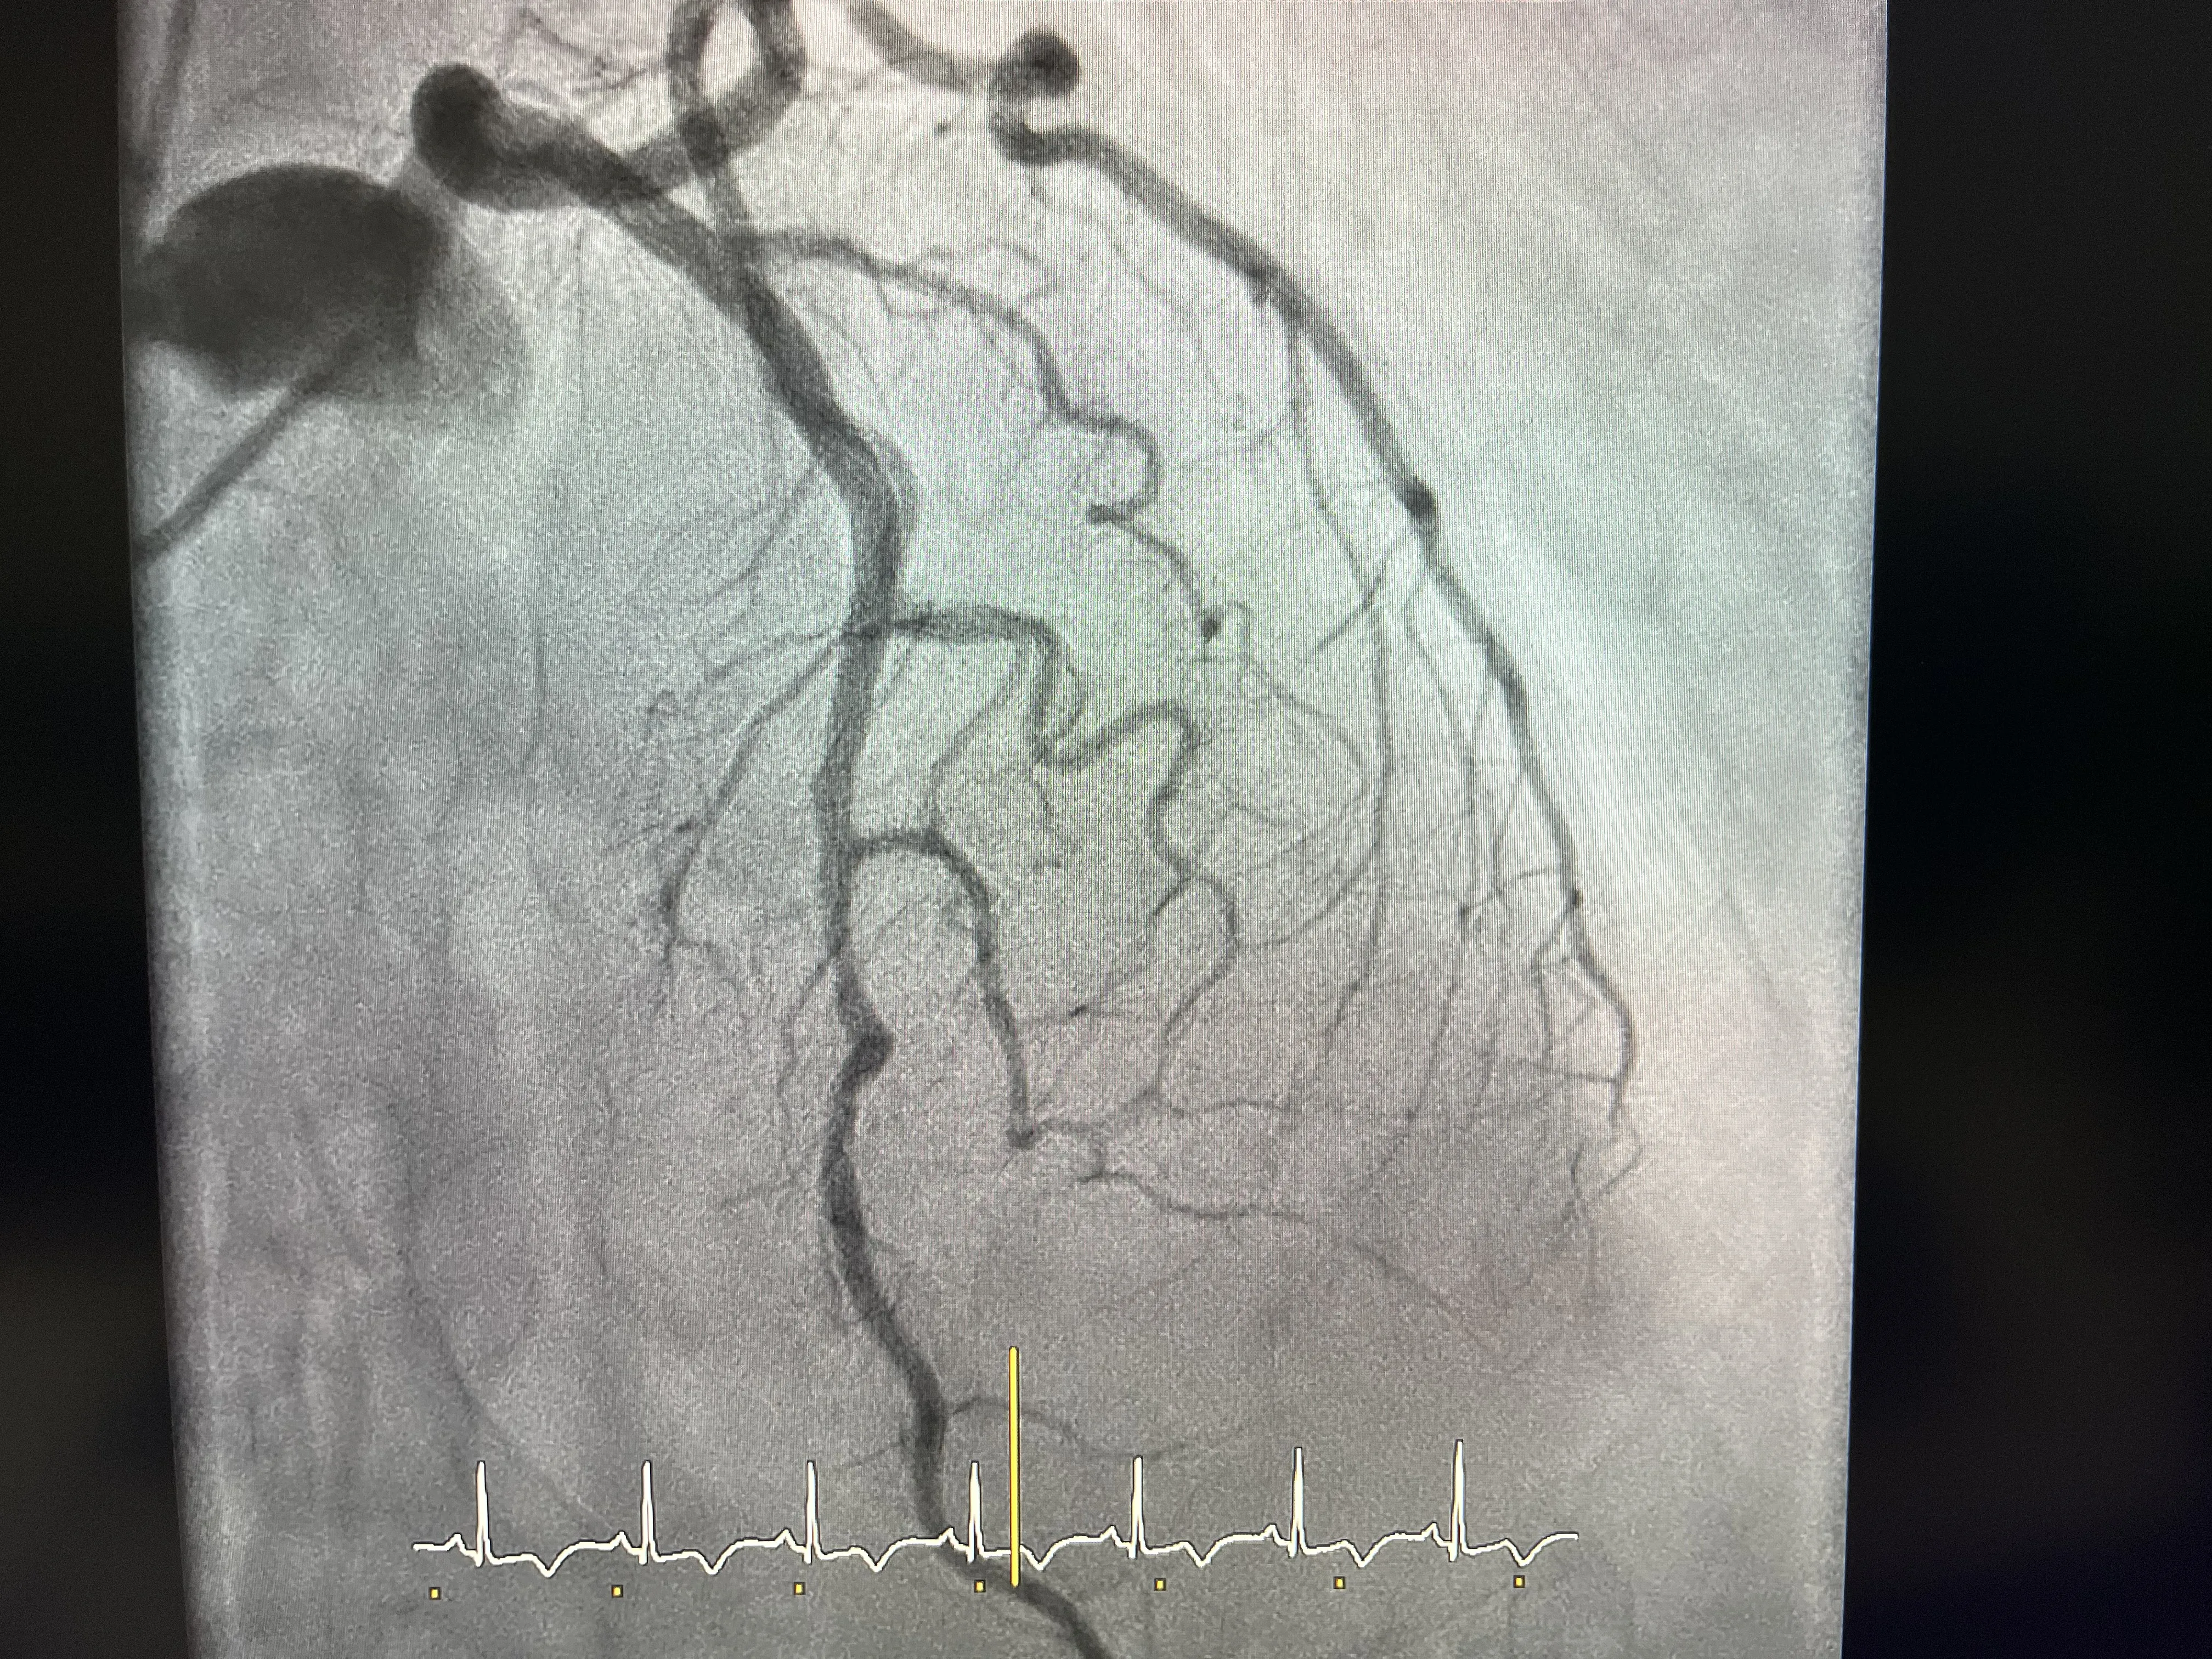

Cateterismo y hallazgo de arterias coronarias sanas

Al realizar el cateterismo en este paciente, lo que se esperaba era encontrar alguna lesión significativa que explicara el dolor y la sospecha de infarto. Sin embargo, el hallazgo fue justo el contrario: las arterias coronarias estaban sanas. La coronaria derecha no mostraba lesiones significativas y la coronaria izquierda tampoco presentaba obstrucciones que justificaran un infarto agudo. Este resultado ya marca un punto de inflexión en el razonamiento clínico.

Encontrarse con unas coronarias sin enfermedad relevante en un paciente con clínica de infarto obliga a replantear el diagnóstico. No es lo habitual en un infarto típico, donde se suele ver una arteria claramente afectada. En este caso, el cateterismo descarta la causa isquémica clásica y abre la puerta a pensar en otras entidades, entre ellas el Takobsubo. Es un momento en el que el equipo tiene que ir más allá de lo evidente y seguir investigando.

Este contraste entre una clínica muy sugestiva de infarto y unas arterias coronarias sanas es una de las claves para sospechar el Takobsubo. No basta con decir que no hay lesiones y quedarse ahí, sino que hay que buscar qué está pasando realmente en el ventrículo. Por eso, tras comprobar que ni la coronaria derecha ni la izquierda tienen lesiones significativas, el siguiente paso lógico es estudiar la función ventricular con más detalle.

El caso que presento es el de un paciente que acudió recientemente con un cuadro muy típico de infarto: dolor torácico, preocupación y una clínica que hacía pensar en un evento agudo. Siguiendo el protocolo, se decidió realizar un cateterismo para valorar las arterias coronarias y actuar con rapidez si había una obstrucción. Todo apuntaba a que se iba a encontrar una lesión significativa que explicara el cuadro, pero la realidad fue otra.

Durante el cateterismo se comprobó que la arteria coronaria derecha no tenía lesiones significativas y que la coronaria izquierda tampoco mostraba enfermedad relevante. Ante este hallazgo, el equipo médico decidió no quedarse solo con la tranquilidad de unas coronarias sanas, sino ir un paso más allá y hacer una ventriculografía. Fue en esa prueba donde se observó la hipoquinesia inferior del ventrículo izquierdo y la imagen típica de jarrón japonés asociada al Takobsubo.